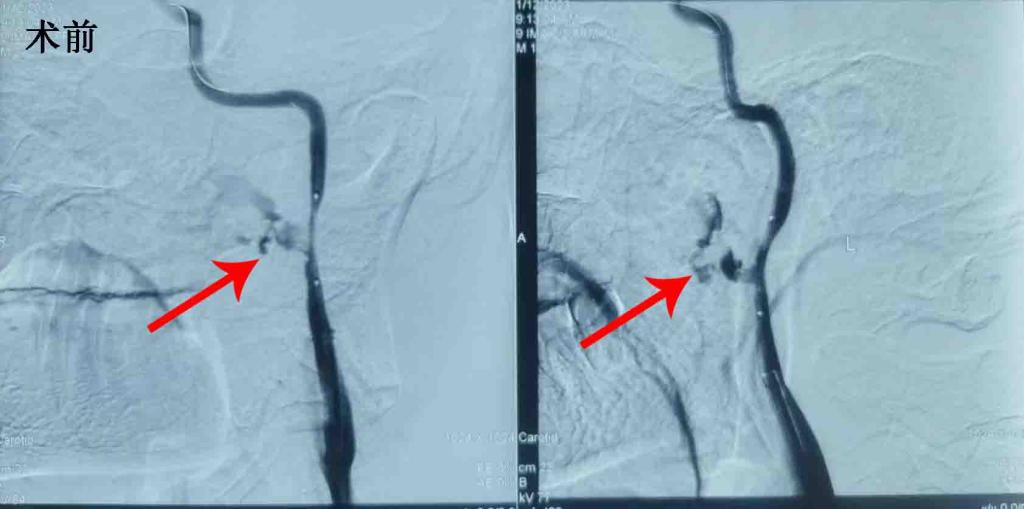

然而,住院期间,患者突发鼻腔、口腔喷射性大量出血,休克血压,张茹副主任医师立即组织抢救,但患者仍出血不止,生命体征不稳定,立即联系输血科紧急配血。鉴于患者鼻咽恶性肿瘤长期放化疗可能引起血管脆性改变,张茹副主任精准判断患者出血可能为颈部血管破裂所致。在家属知情同意下,联系耳鼻喉科、麻醉科予以气道保护,局麻下急诊行脑血管造影,发现患者喷射性出血确系左侧颈内动脉破裂所致。颈动脉破裂出血是严重的大血管出血性疾病,死亡率极高。造影期间,患者仍有口咽部及鼻腔大量出血,窒息风险极高,需要紧急止血,紧急联系介入科、神经外科现场讨论形成共识:患者左侧颈内动脉破裂出血诊断明确,病情极其危重,应立即进行覆膜支架植入术。立即借调覆膜支架,期间采用球囊血管内间断压迫法止血。最后在神经内科张茹副主任医师、神经外科许刚副主任医师、张磊住院总医师、樊洪医师协作下,完成了左侧颈动脉破裂部位覆膜支架植入术,术后患者出血很快停止,生命体征逐渐稳定,后于入我科监护病房输血、补液等治疗。目前患者未在出血,头痛明显缓解,体温正常,已脱离病危状态。

图2 左侧颈内动脉破裂出血覆膜支架植术前术后对比,术后出血立即停止。